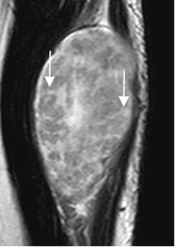

Fig 178 A. Signo fascicular.

RM sagital en T2. Imágenes anulares y de bordes hiperintensos, por lesión de origen neurogénico